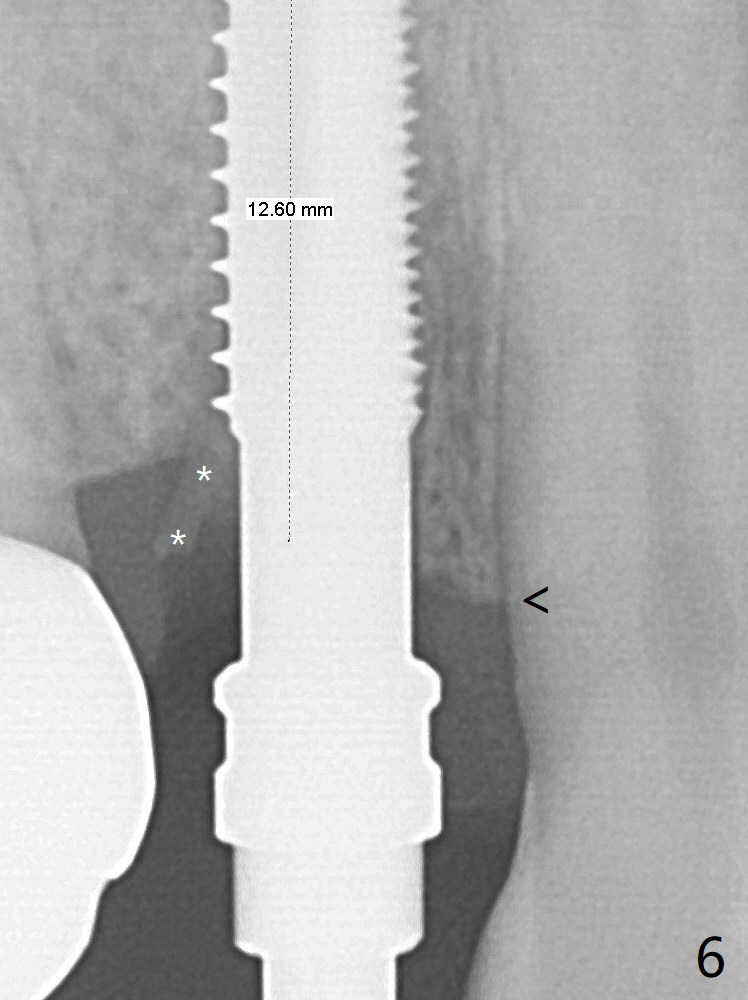

With the 2nd redirection (Fig.6 (4.5 mm tap, mesial crest (<) much lower than the distal one)), a 4.5x12 mm implant is placed with 50 Ncm; bone graft is placed with emphasis on the palatal defect (Fig.7 *). As usual, an immediate provisional is fabricated. In fact the abutment may be not completely seated because of contact with the mesial crest (<). After 5.5 mm profile drill 11 months postop, the abutment has no contact with the mesial crest (Fig.8 <).